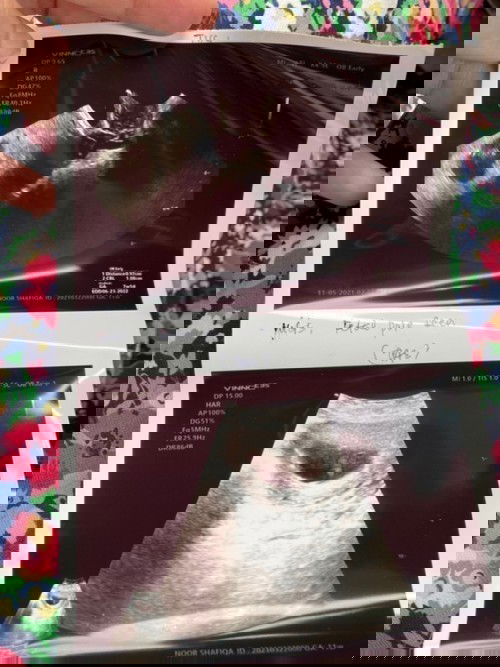

Salam, ada tak siapa yang ada pengalaman scan baby awal2 1st trimester tenggelam timbul2 bila scan? Saya risau, haritu scan 6 week dah nampak jantung dengan janin, lepas 3 weeks tu last week saya scan semula, waktu scan tak nampak baby.. baby macam tenggelam timbul macam tu.. Bila scan ada nampak jantung, cuma doc tak dengar je sebab kecik lagi.. Gambar bawah ialah last week scan.. Dan harini pulak saya scan lagi lepas seminggu, sama saja tenggelam timbul baby.. doc takut janin tak membesar ikut weeks, dr suruh saya tunggu 2 minggu utk scan semula.. tadi pulak scan macam lagi teruk lak nampaknya berbanding lepas, tak dapat nak ukur baby berapa weeks.. Yang ni second pregnancy saya, first saya miscarriage awal bulan 4/21. Saya sangat risau, doakan saya ada rezeki baby kali ini 😭 #advicepls #1stimemom #pleasehelp #firstbaby